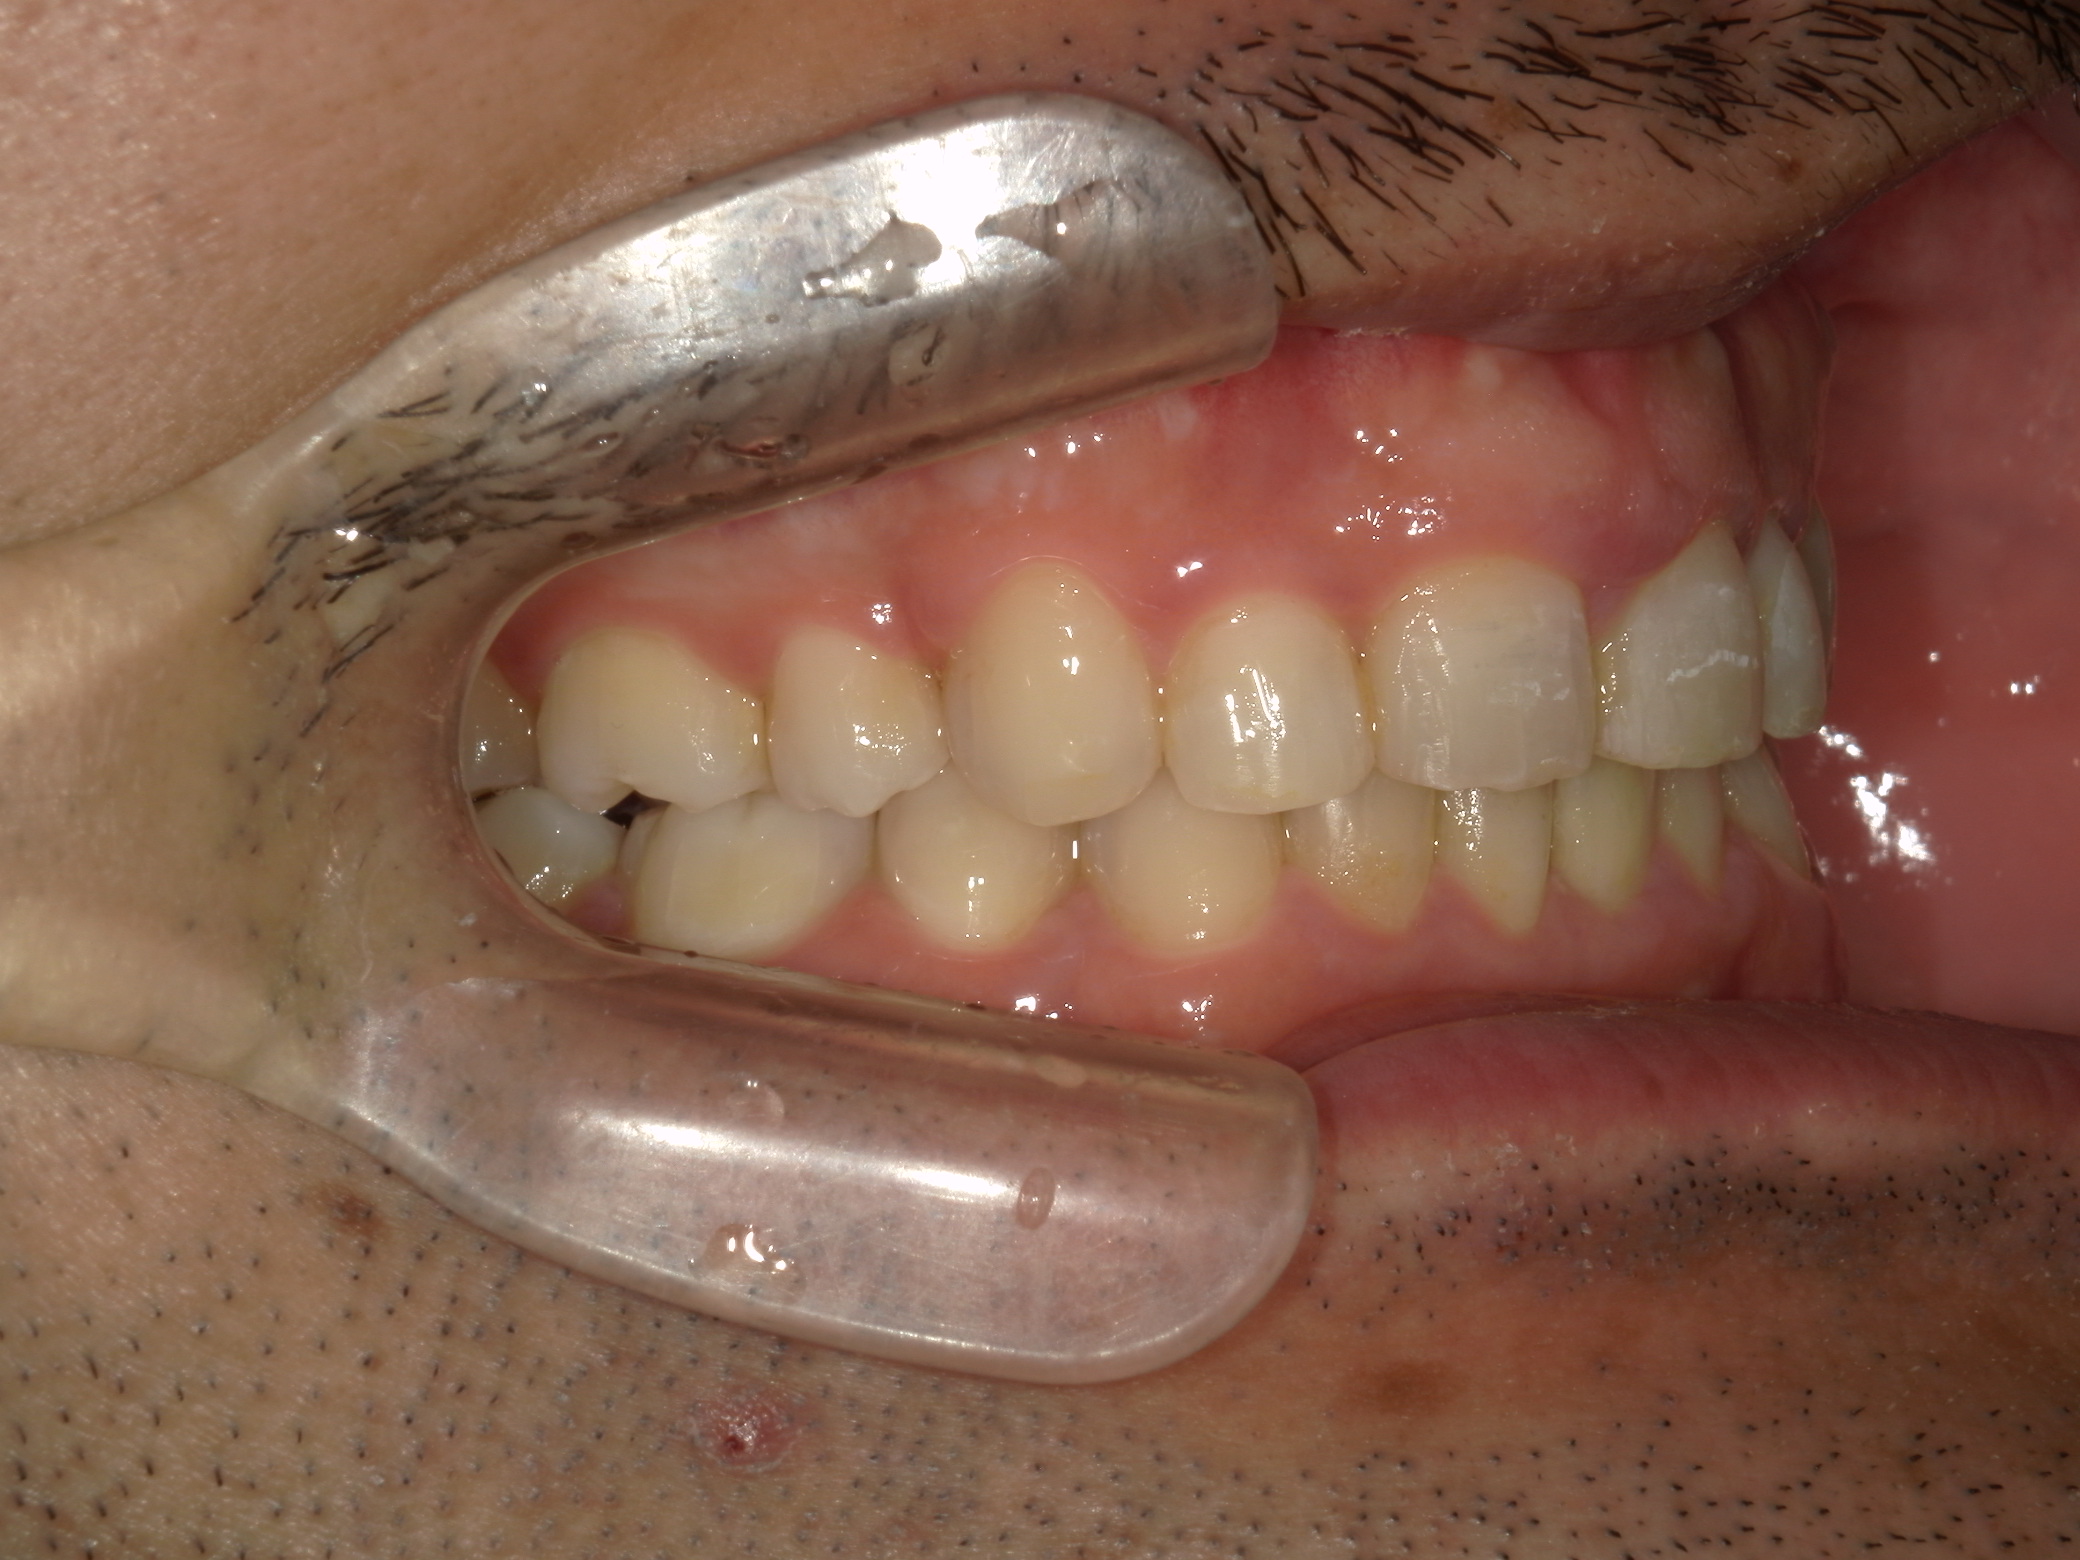

全顎ワイヤー矯正 症例(79)

主訴: 前歯が噛み合わない。歯並びが気になる。

カテゴリー : ガタガタ(叢生) , 噛み合わせが深い(過蓋咬合)